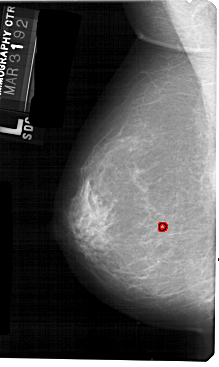

A_1599_1.RIGHT_CC

RIGHT_MLO LINES 5326 PIXELS_PER_LINE 2716 BITS_PER_PIXEL 12 RESOLUTION 43.5 OVERLAY

FILE: A_1599_1.RIGHT_CC.OVERLAY

TOTAL_ABNORMALITIES 1

ABNORMALITY 1

LESION_TYPE MASS SHAPE ASYMMETRIC_BREAST_TISSUE MARGINS OBSCURED

ASSESSMENT 2

SUBTLETY 5

PATHOLOGY BENIGN_WITHOUT_CALLBACK

TOTAL_OUTLINES 1

BOUNDARY